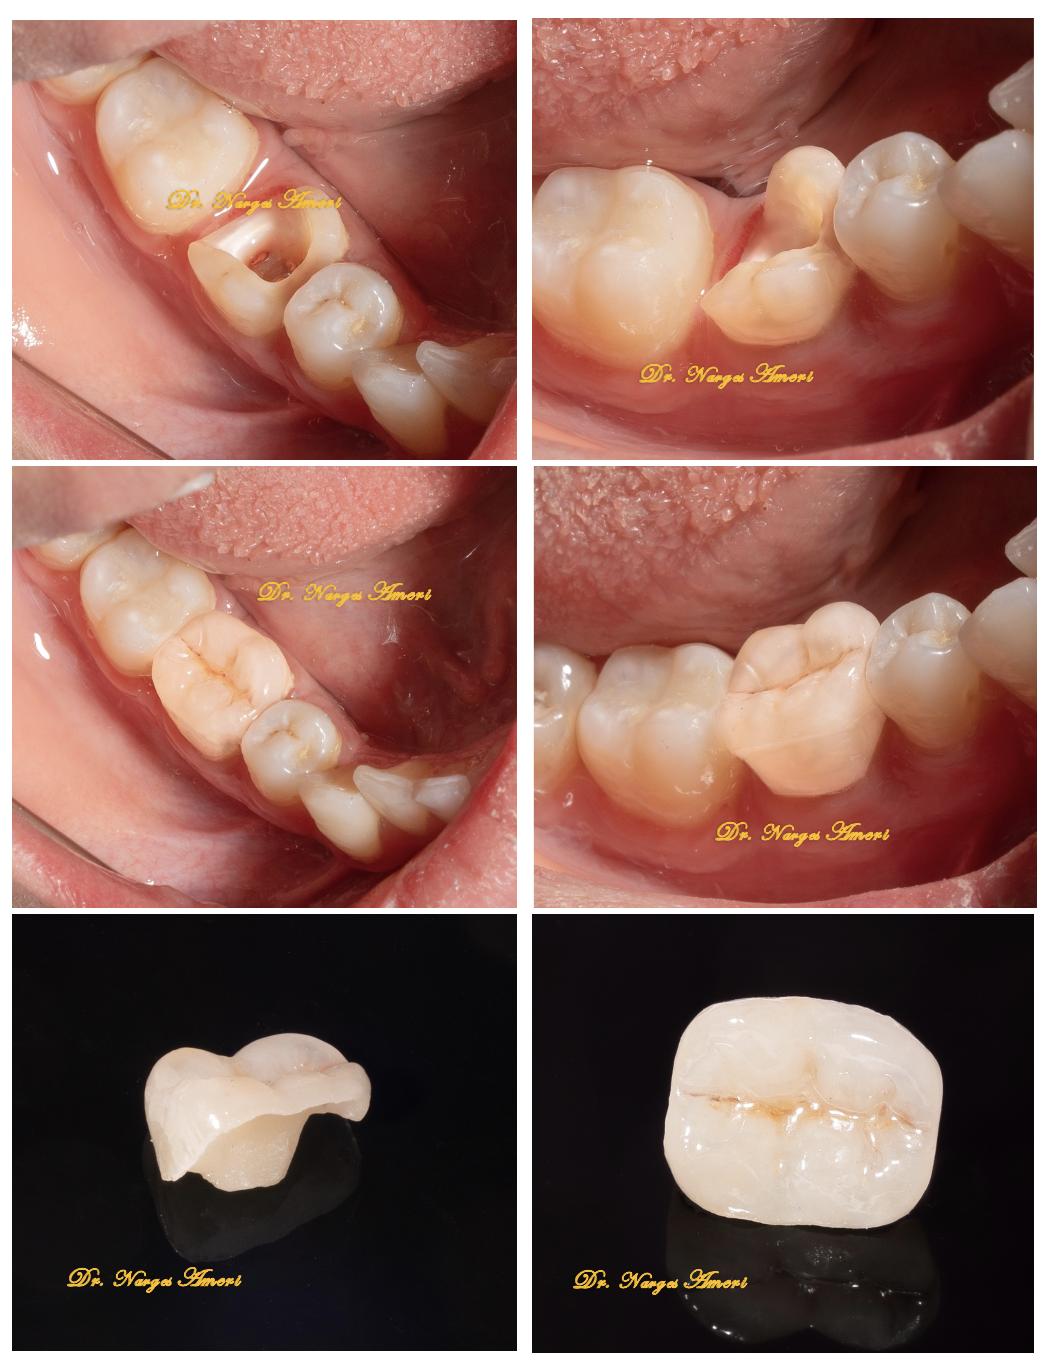

Endocrown Restoration

Conservative endocrown restoration preserving maximum tooth structure